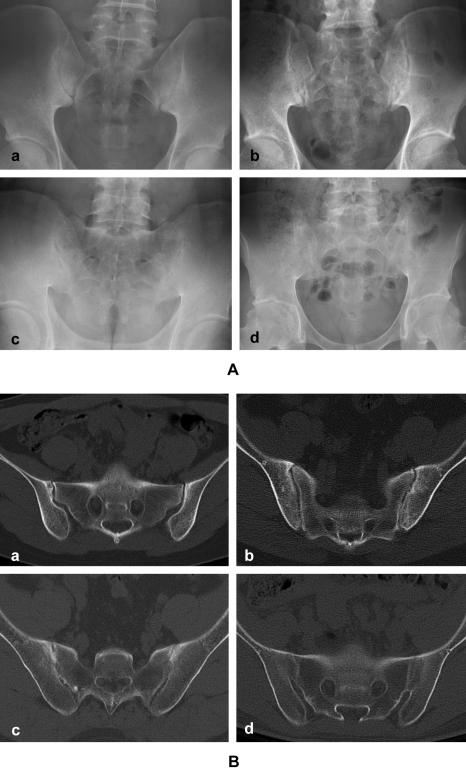

Due to the low sensitivity of plain radiography, the diagnosis of early stage ankylosing spondylitis (AS) is often difficult since many patients do not meet the radiographic criteria. The objective of our study was to investigate the diagnostic value of performing multidetector computed tomography (MDCT) of the sacroiliac (SI) joint in the evaluation of AS patients.

Thirty seven patients with definite or probable AS were evaluated. Plain radiography and MDCT imaging of the pelvis were performed for evaluating the SI joints. Two radiologists analyzed the images, and they graded the sacroiliitis on a scale of 0-4 according to the modified NY criteria. The clinical variables we analyzed included the disease duration, the treatment duration, the prescribed drugs, peripheral joint involvement, enthesopathy, the functional limitations and the BASDAI.

MDCT detected more bilateral sacroiliitis as compared to the plain radiography (86.5% vs. 75.7%, respectively), and MDCT yielded a higher grade of disease in 32.4% (right SI joint) and 24.3% (left SI joint) of the patients. More patients satisfied the modified NY criteria with using MDCT as compared with that when using the plain radiography (81.1% vs. 54.1%, respectively, p=0.002).

Visualization of the sacroiliac joint by MDCT provided a better diagnosis of AS, and especially during the early stage of the disease.